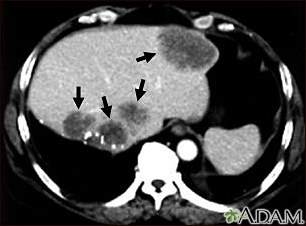

Liver metastases, CT scan